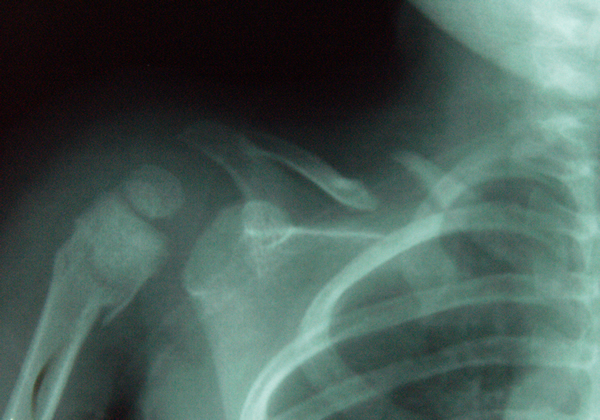

I genitori si sono recati presso un altro ospedale dove l'esecuzione della radiografia ha per� riservato delle sorprese. Essa, infatti, secondo l'ortopedico evidenziava (figura 1):

a) Frattura della clavicola (si notava il caratteristico disassiamento dei due monconi, il prossimale verso l'alto, dovuto alla trazione del muscolo sternocleidomastoideo e il moncone prossimale verso il basso, grazie all'azione combinata dei muscoli deltoide, gran pettorale e succlavio).

b) Frattura prossimale dell'omero destro, ma risalente ad almeno venti giorni prima e gi� in fase di guarigione.

I segni radiologici sono abbastanza caratteristici: i margini dei monconi sono smussi, arrotondati, claveati, ipercaptanti, ma, soprattutto, i bordi dei due capi non collimano come succede nel caso di un vera frattura (4).